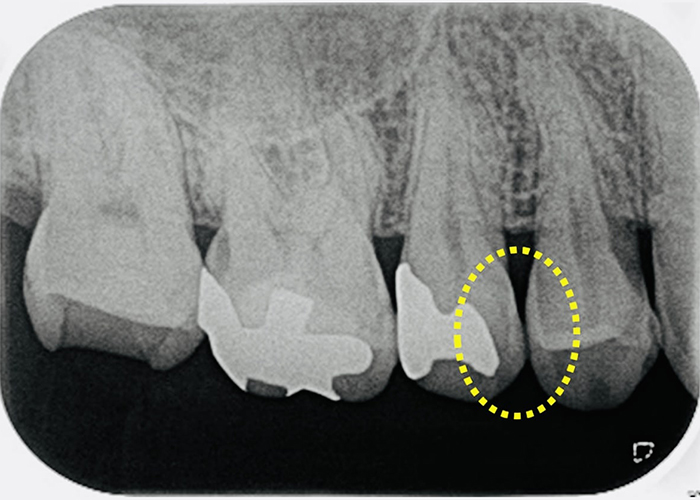

虫歯が疑われたが削らずに済んだ例

視診では歯間部が黒く透けており虫歯が疑われ治療が必要そうな状態 |

レントゲンでは虫食い状に黒く写ってはないので深く虫歯は進行してはいないと判断した |

レーザー診断にて数値が「40」だったため『初期虫歯』と判断し、削らず経過観察とした。 |

このように数値で虫歯の進行状況がわかるため、なるべく削らない治療が可能です。

当院では61以上の数値で治療が必要と判断します。

視診では歯間部が黒く透けており虫歯が疑われ治療が必要そうな状態

レントゲンでは虫食い状に黒く写ってはないので深く虫歯は進行してはいないと判断した

レーザー診断にて数値が「40」だったため『初期虫歯』と判断し、削らず経過観察とした。